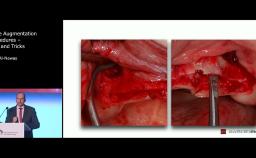

The congress lecture will discuss two techniques for sinus floor elevation (SFE) in implant dentistry: the lateral window technique and the transalveolar technique. Choice of method depends on anatomical considerations such as residual bone. Both methods show high implant survival rates, comparable to native bone (around 95%). Transalveolar SFE is suited for cases with enough residual bone and a flat sinus floor, but risks Schneiderian membrane perforation due to incomplete osteotomy. Advances in surgical instruments, including drills with safety ends and controlled hydraulic pressure, have reduced perforation risks in transalveolar SFE. However, for severely resorbed ridges or the presence of septa, the lateral window technique is preferred. The lecture will cover how to select the appropriate technique for each patient.

- determine when to use the lateral window technique and transalveolar technique

- determine the extent of the elevation of the Schneiderian membrane during the lateral window technique